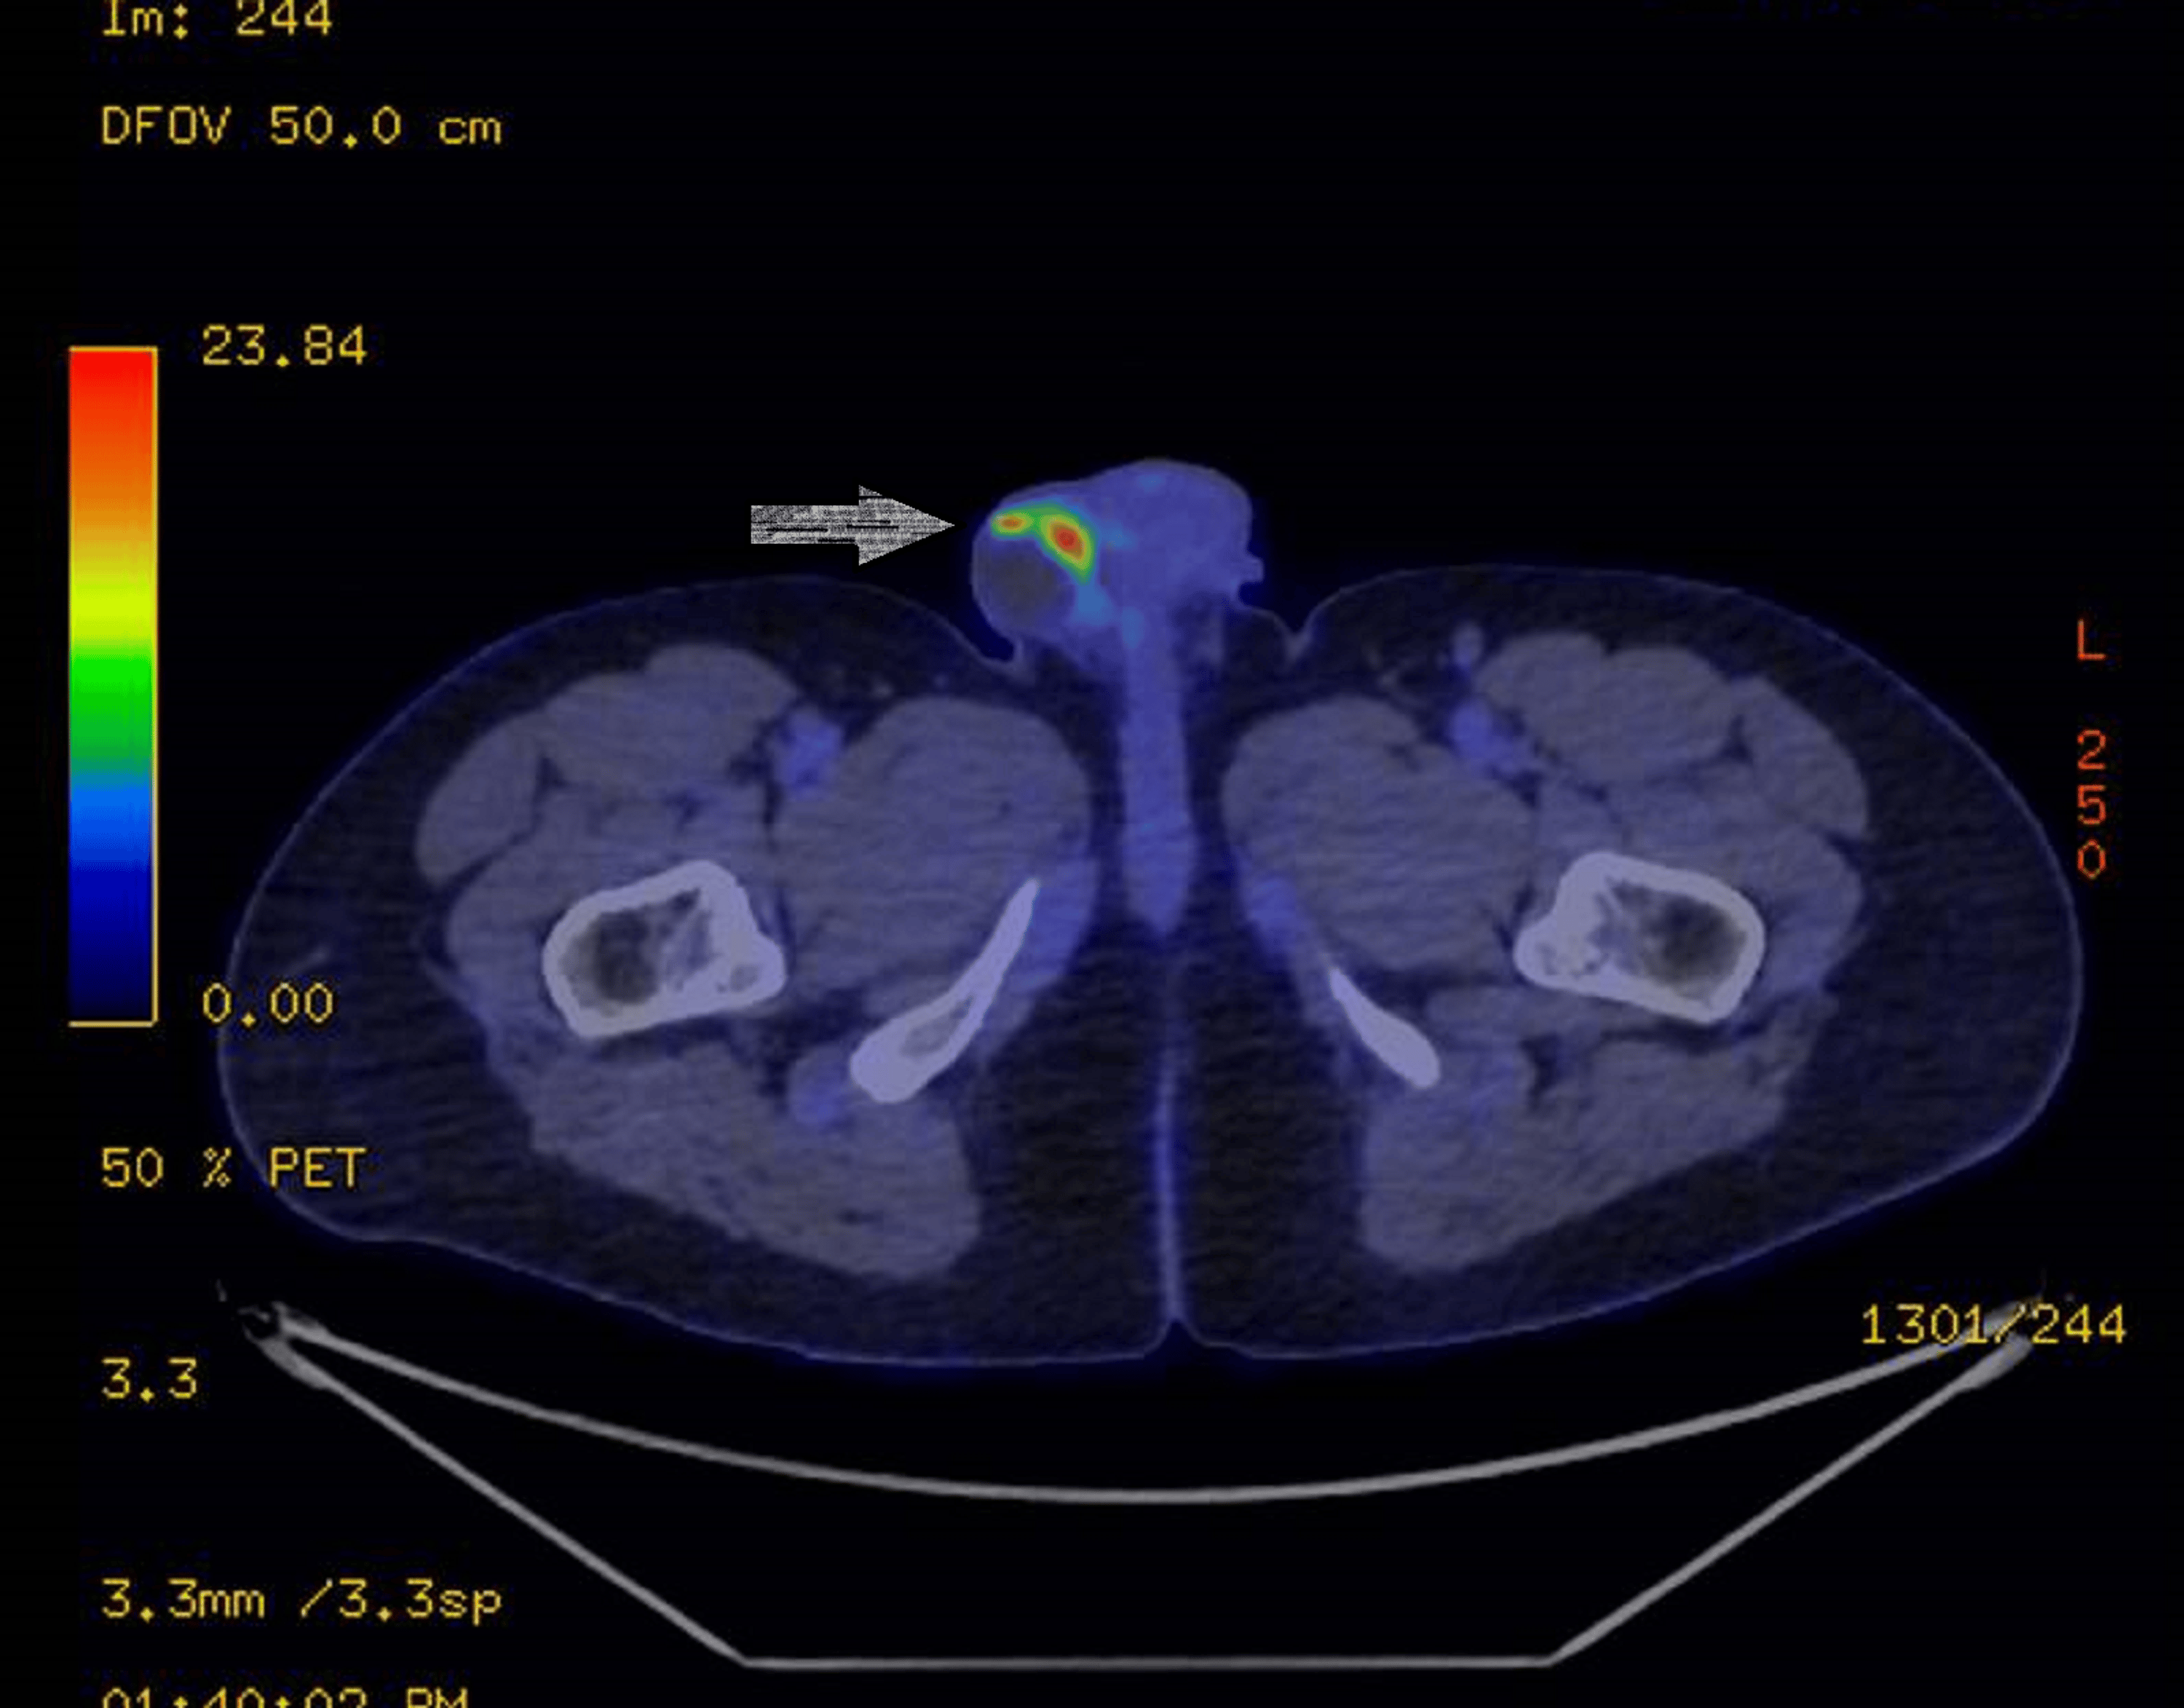

Testicular tumor imaging Testicular Cancer Rare Most testicular cancers start in cells known as germ cells and. Among the different stages of germ cell tumors, pure. Treatment for testicular cancer is based mainly on the type and stage of the cancer. Stromal tumors are sometimes referred to as gonadal stromal tumors. Failure of the testicles to descend into the scrotum, a condition called. They grow and. Testicular Cancer Rare.